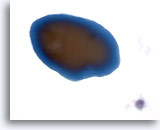

Positivo per carcinoma papillare

I campioni appartenenti a questa categoria sono quelli in cui all’istologia viene individuata una patologia maligna nel 100% dei casi. Il carcinoma papillare costituisce il tumore maligno della tiroide più diffuso e presenta caratteristiche nucleari specifiche facilmente identificabili nei campioni citologici. Altre patologie maligne diagnosticabili con un elevato grado di accuratezza grazie alla citologia sono: carcinomi midollari, linfomi e carcinomi metastatici. Nei campioni ThinPrep il carcinoma papillare è è caratterizzato da lembi e aggregati papillari di cellule affollate con nuclei ingranditi e a stampo, cromatina “polverosa”, membrane nucleari irregolari messe in evidenza da solchi nucleari e inclusioni citoplasmatiche intranucleari e nucleoli piccoli ma prominenti e spesso eosinofili. [7] Al contrario, il carcinoma midollare è caratterizzato da cellule plasmocitoidi monomorfe isolate con un rapporto N/C elevato, nuclei eccentrici e cromatina vistosamente granulare con o senza nucleoli prominenti. Il citoplasma è granulare con granuli piccoli e appena visibili. In alcuni casi, le cellule appaiono affusolate, ma presentano le stesse caratteristiche nucleari. I linfomi e i carcinomi metastatici della tiroide sono molto meno diffusi. Le caratteristiche citologiche dipendono, nell’ordine, dall’istotipo e dal sito di origine.